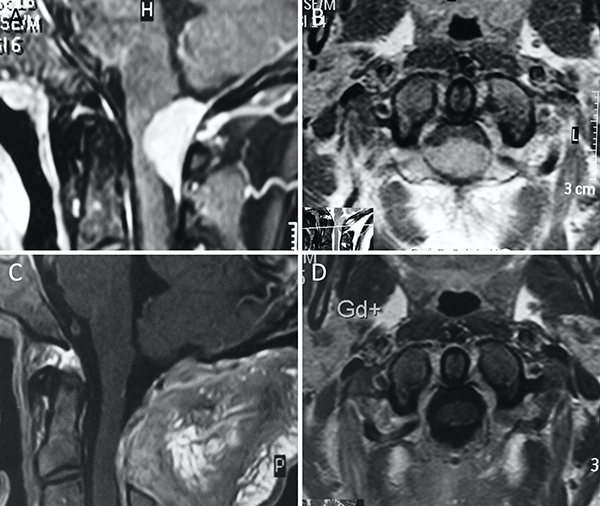

Figura 4. Meningioma petro-clival. A-B: RM preoperatoria; C-D: RM postoperatoria.

Figura 9. Meningioma del foramen magno anterior. A-B: RM preoperatoria; C-D: RM postoperatoria.

Figura 10. Meningioma del foramen magno lateral. A-B: RM preoperatoria; C-D: RM postoperatoria.